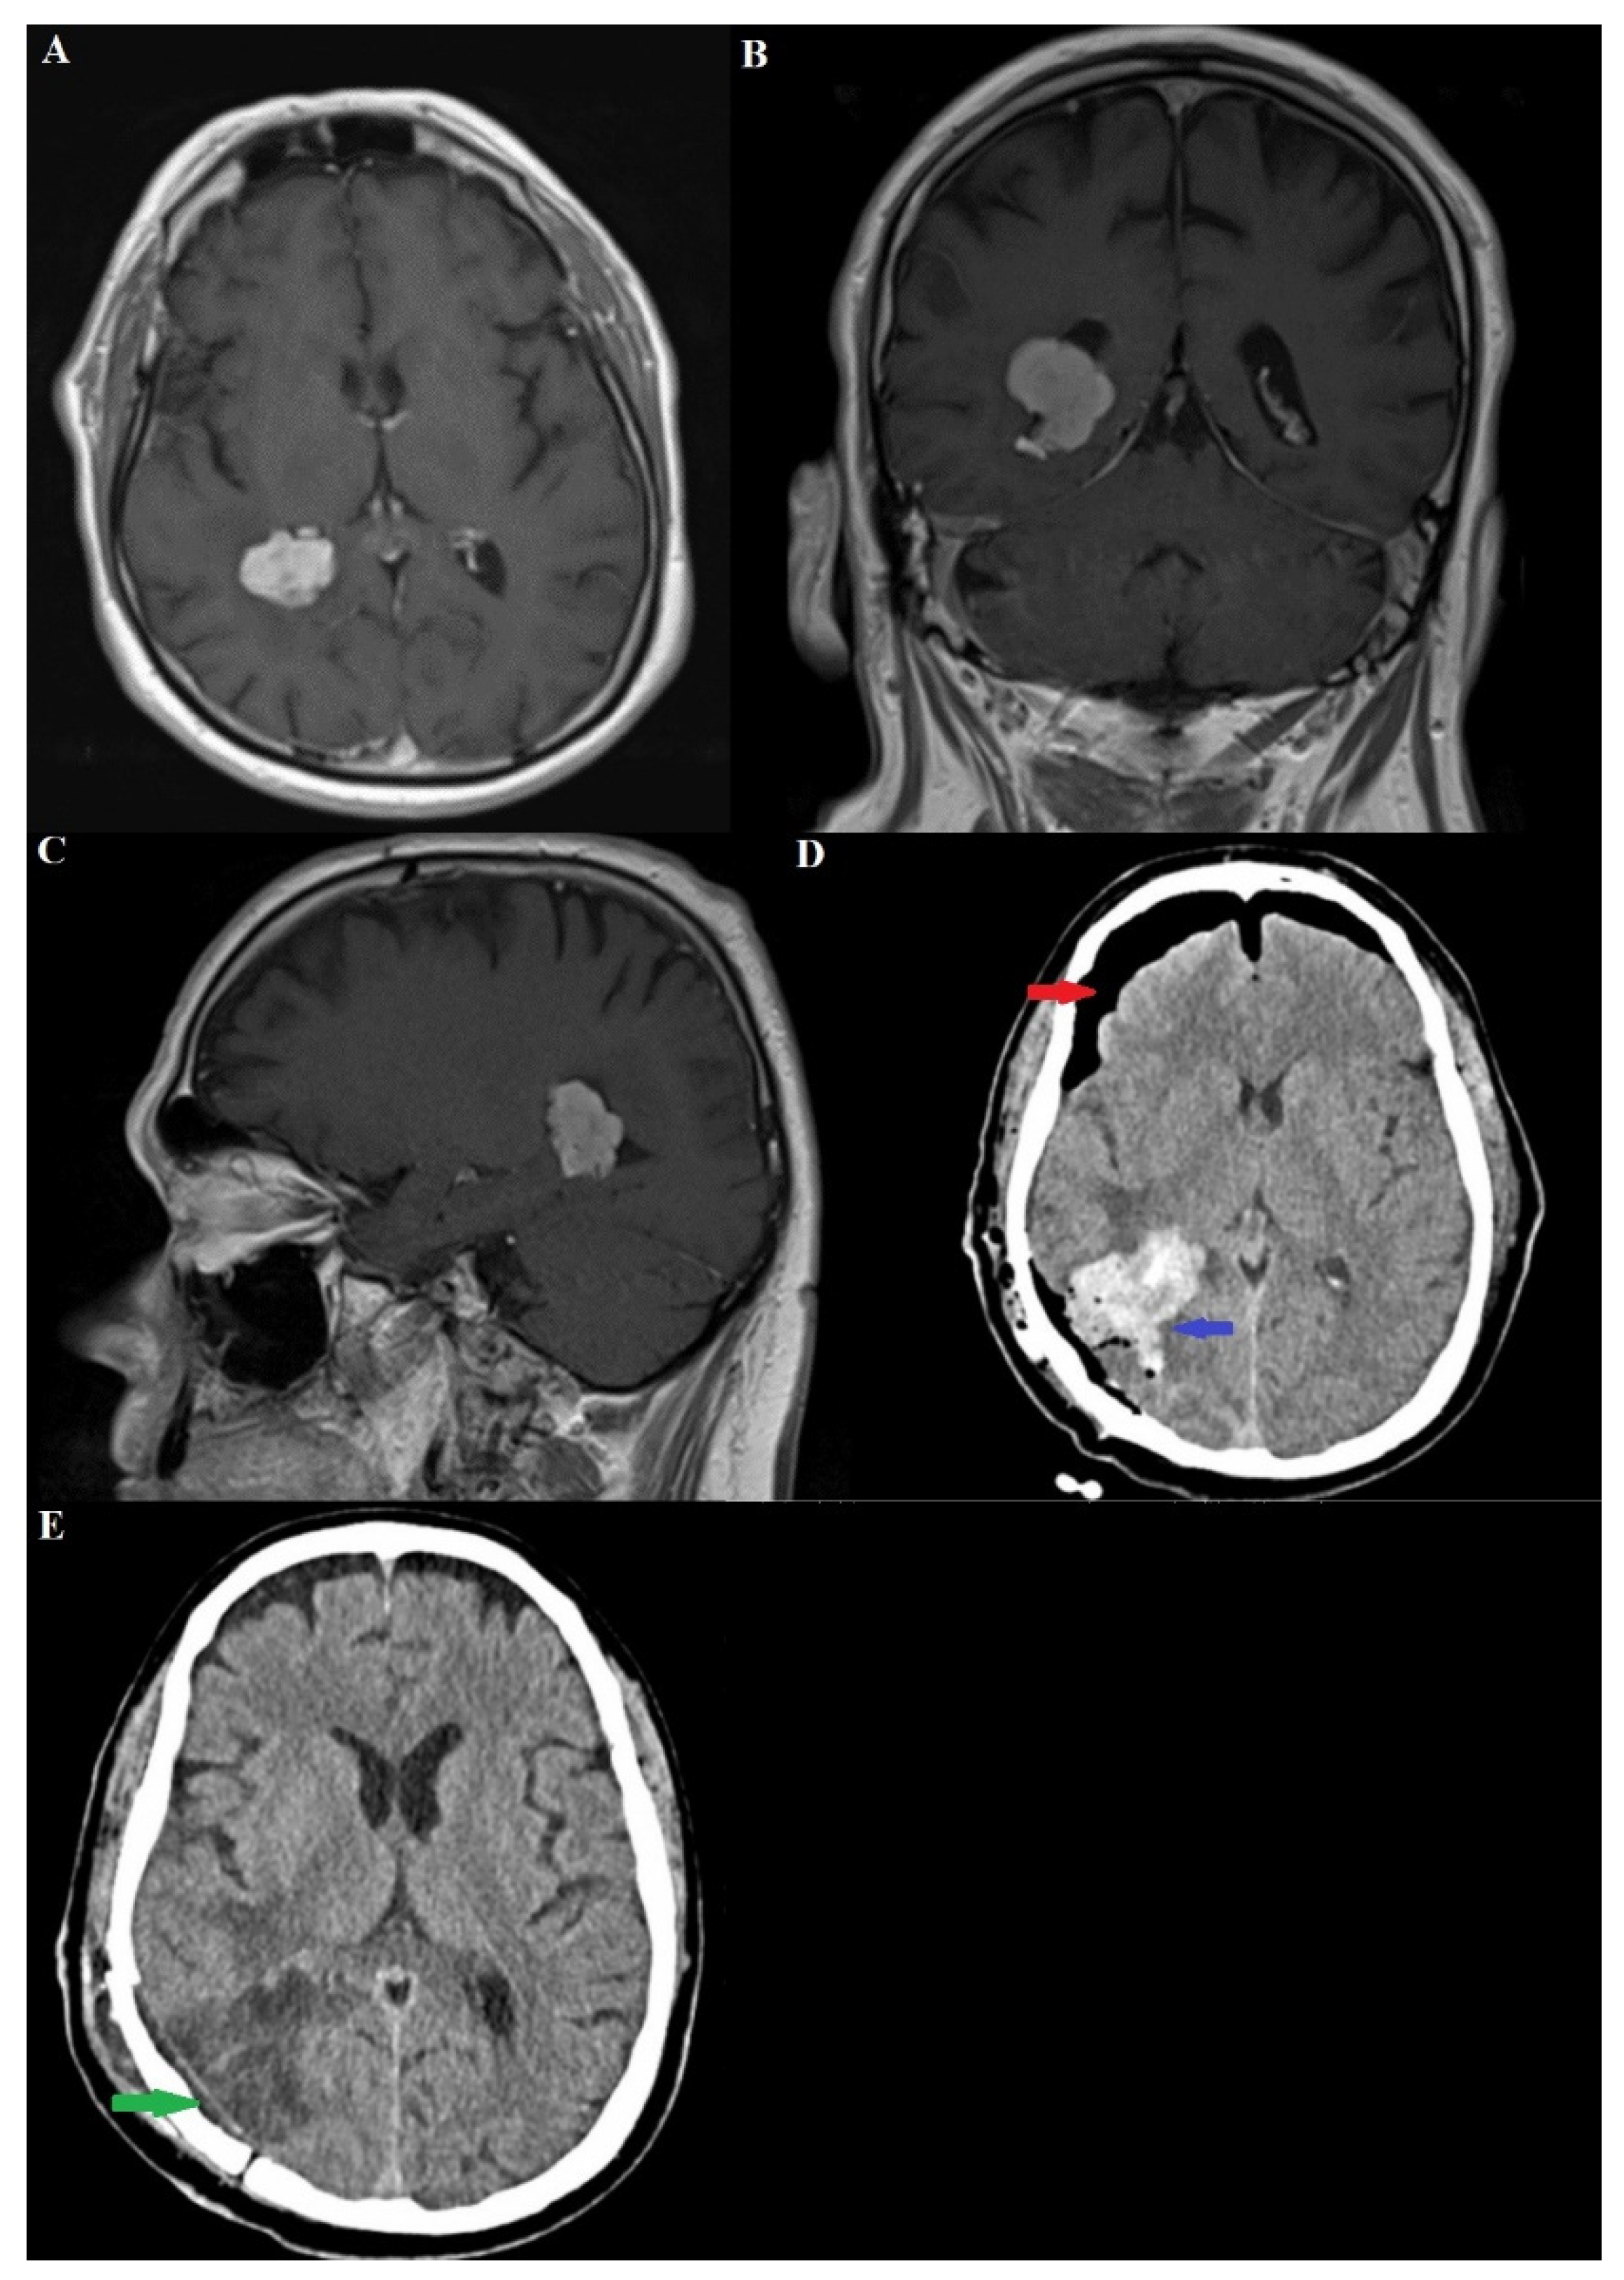

2.1. Clinical Features and Diagnostic Imaging Results

| Case 4 [Present case] | 66/M | Persistent headache for 2+ months, no neurological deficits | Choroid plexus papilloma and meningioma—trigone of the right lateral ventricle—2.45 cm | Contiguous | Total surgical resection; treatment for transurethral tumor initiated |